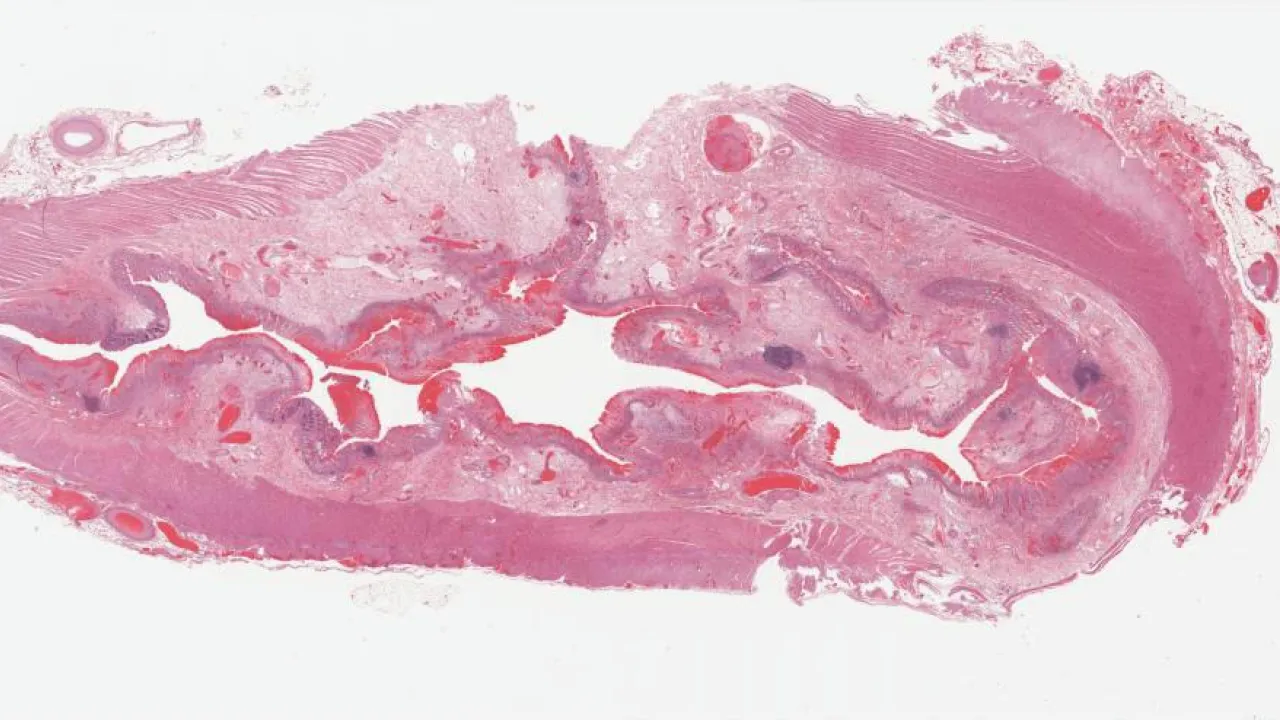

Lower GI Tract, Mucosal injury due to sevelamer